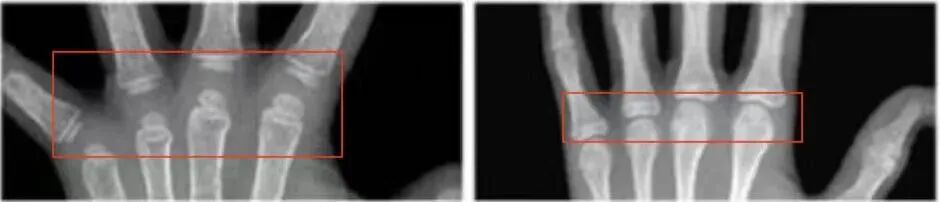

注:框內(nèi)為第3百分位,對應年齡低于框內(nèi)數(shù)值,需及時就醫(yī)

(骨齡小時,骨間距相對較大)

(骨齡越小,腕骨數(shù)量、密度越小)